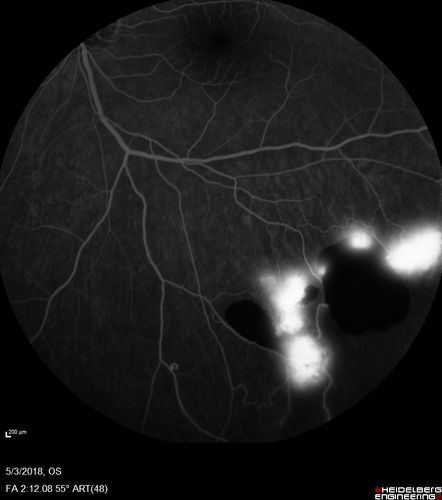

Coats' Disease -51 year old asymptomatic male

20/20 vision - had laser to non-perfusion because of proliferation.

Coats' Disease 51 yo Male - Asymptomatic